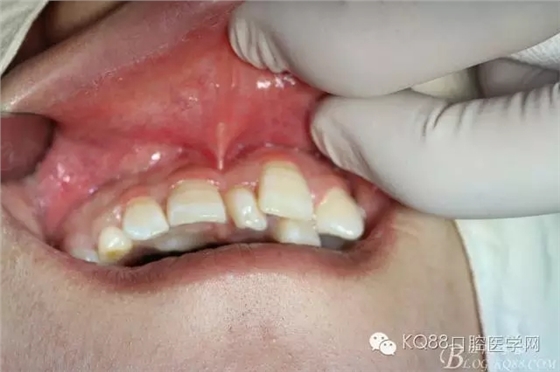

圖1.患者11與21之間有一多生牙、53滯留、13未見萌出、11松動Ⅰ度